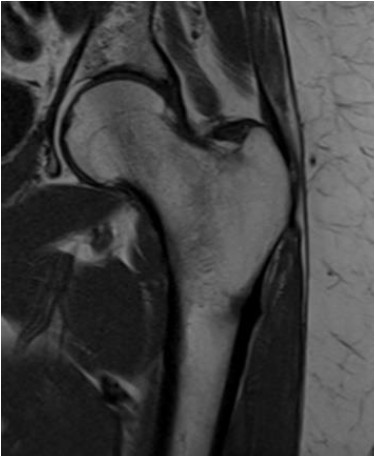

Paciente de 56 anos com dor no quadril após queda realizou exame para elucidação diagnóstica demonstrado na imagem abaixo.

De acordo com a imagem, o exame realizado e o plano de aquisição são, respectivamente: